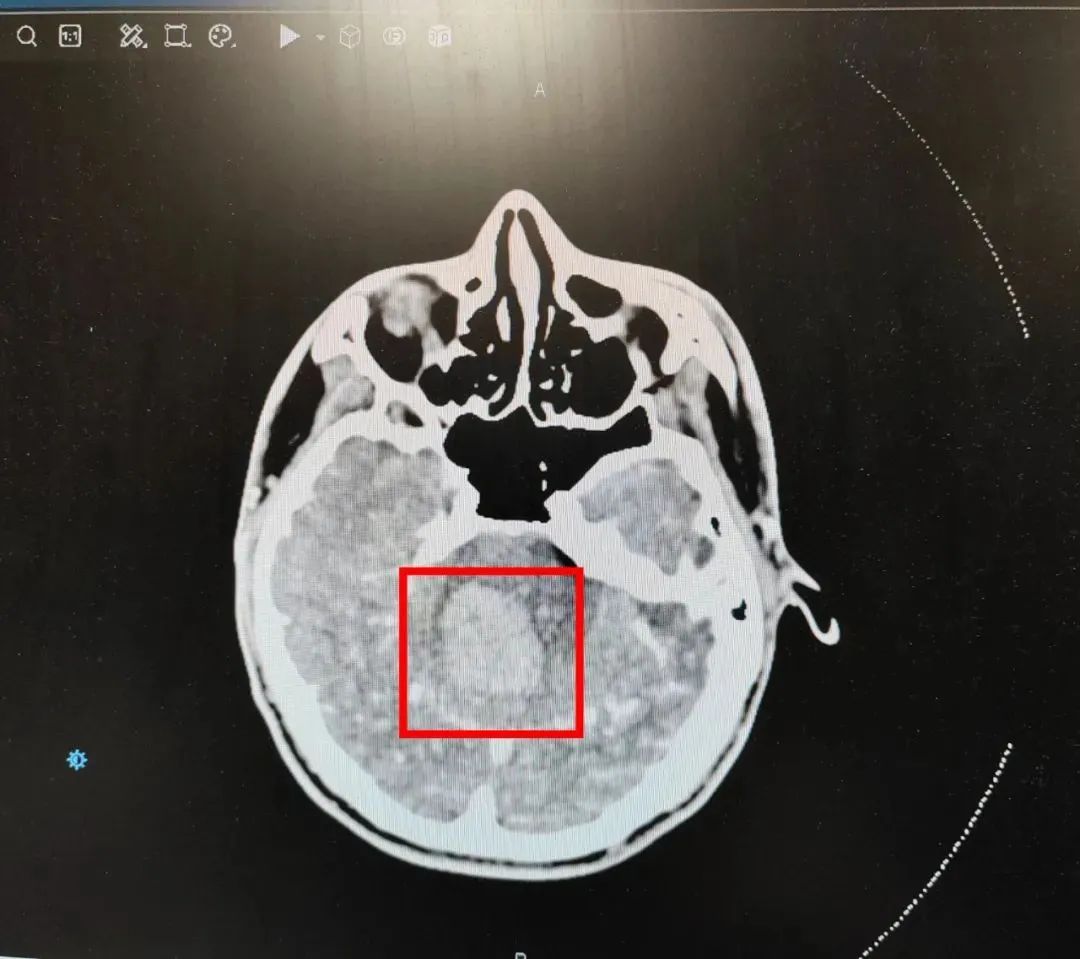

图为该患者脑出血部位

脑出血是脑内血管破裂

血液压迫脑组织导致脑损伤